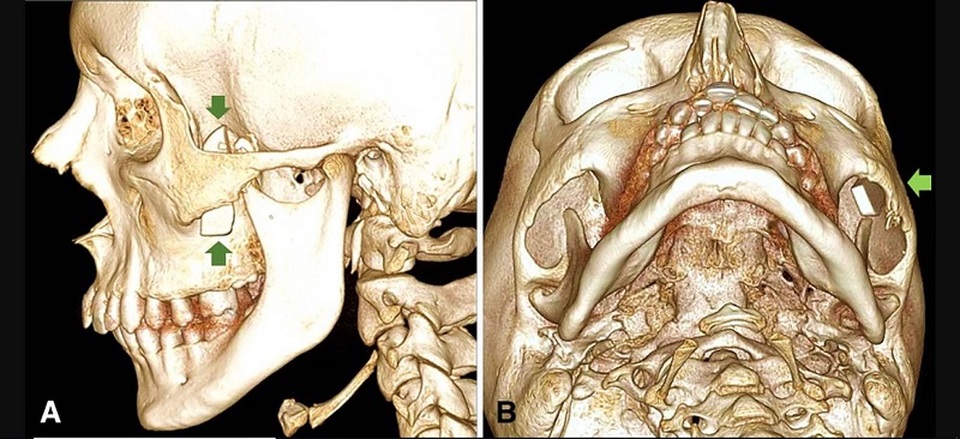

Hình ảnh chụp CT 3D hộp sọ của cậu bé cho thấy mảnh kính vỡ nằm phía sau xương má.

Do đó bác sĩ tiếp tục cho cậu chụp CT, và hình ảnh rõ nét hiện ra giống như một mảnh lưỡi dao sắc nằm trong xương má cậu bé. Đây là trường hợp rất hy hữu bởi vì vùng mặt này được xương má bảo vệ, rất khó để một vật xuyên qua.